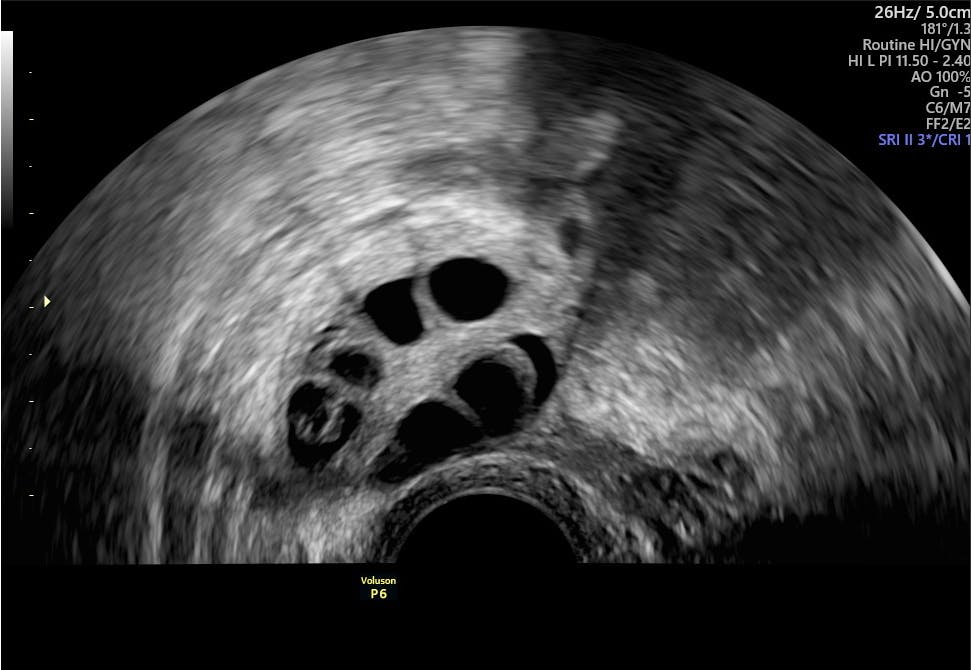

Around 1 in 10 females of childbearing age have the condition known as PCOS Polycystic Ovary Syndrome. Polycystic ovary syndrome PCOS is one of the common endocrinopathies of women in the reproductive age group. Polycystic ovary syndrome can be very different from person to personcausing different grades of metabolic or menstrual cycle irregularities 10 11.

As the prevalence of these endocrine dysfunctions increases the association of polycystic ovary syndrome PCOS and autoimmune thyroid disease. Hypothyroidism is a disorder pertaining to low thyroid hormone levels and PCOS refers to a disorder consisting of high hormone androgen hormones levels in women They have similar symptoms that can sometimes cause misdiagnosis. To evaluate and detect the thyroid dysfunction in patients with PCOS.